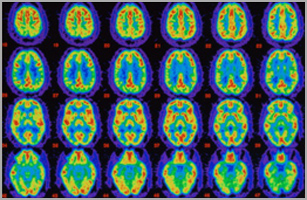

Reise durchs Gehirn

Führen Sie die interaktive Reise durchs Gehirn durch, um mehr über die Wirkung von Alzheimer auf die Gesundheit des Gehirns zu erfahren.